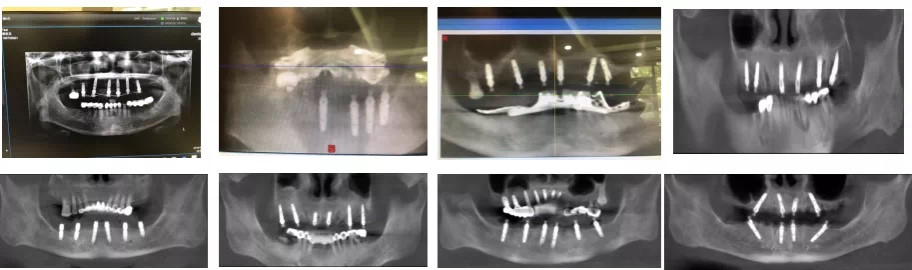

追求完美这件事,也同样体现在他对种植牙的研究上,13年来他积累了口腔各类种植案例10000余例。

随着科学的进步和发展,越来越的患者通过数字化种植,重新获得了咀嚼的能力和自信的微笑。